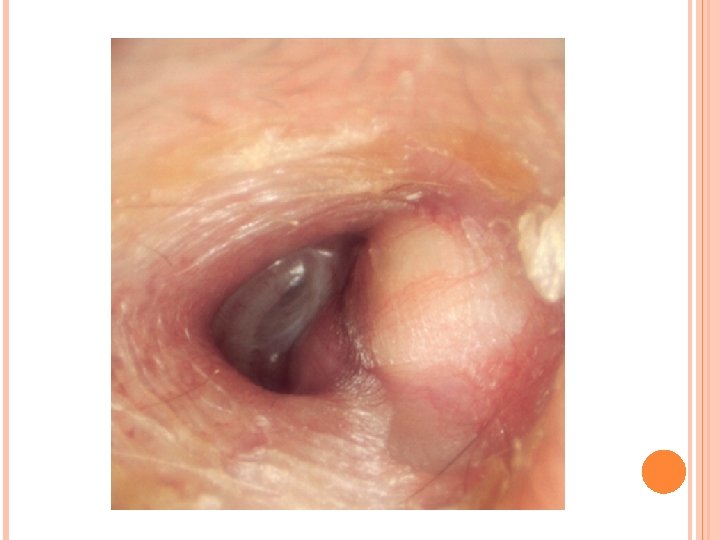

TUMORES DEL OIDO EXTERNO Tumores benignos Osteoma Es un tumor de formación osea que se producen en la porción ósea del CAE, y pueden ser múltiples. Los síntomas son hipoacusia y malestar en el oído. El tratamiento consiste en la extracción quirúrgica. Exostosis Son los tumores más frecuentes del CAE. Está relacionado con exposición por largo tiempo con agua fría y es por esta razón que se ve muy frecuentemente en nadadores. Se ven lesiones redondeadas multiples en el CAE, muy duras, cubierta de piel normal. Los síntomas dependen del tamaño, al inicio asintomáticos, luego hipoacusia de conducción, produce dificultad para la limpieza. Se trata quirugicamente. Adenomas: tumor de glándulas sebáceas. Ceruminoma: tumor de glándulas sudoríparas. Otros: condroma, hemangioma, lipoma, fibroma, linfangioma, papiloma, neurilemoma.